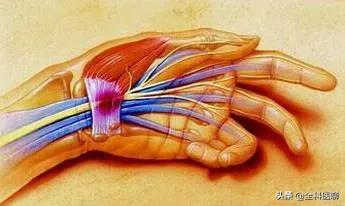

手根管の正中神経が圧迫されることによって、人差し指と中指の痛みやしびれ、親指の筋力低下が起こる症状である。

手のしびれは、手首付近の前腕から手のひらにかけて走る神経が圧迫されることによって誘発され、痛み、灼熱感、ピリピリ感などの不快感を伴い、時には手の脱力を伴うこともある。

神経損傷というと、外傷、腫瘍、手根管症候群などが神経損傷につながる可能性があり、特に正中神経、尺骨神経、橈骨神経が損傷され、指がしびれたり、痛んだりすることがあります。手根管症候群は、例えば、その形成の主な理由は、患者の手首の正中神経が圧迫されるにつながる長い時間の手首の不適切な使用であり、この種の患者は、しびれ、あるいは痛みの3本の指の親指側に表示されます。

3つ目は手根管症候群で、手根管が圧迫され、手根管を通る神経が損傷し、指のしびれや痛みが生じる。

最も多いのは手首の神経巻き込みで、手首にはブレスレットのような靭帯があり、手首の神経や血管を縛っている。 この縛りがきつすぎると巻き込みが起こり、通常、神経、靭帯、腱が長時間摩擦されることで炎症や水腫が起こり、その結果、押し出されて神経が巻き込まれる。

手根管症候群と呼ばれる正中神経の圧迫の場合、親指側の3本の指のしびれや、親指側の手掌面の筋萎縮が起こることもある。

3.手根管症候群

手根管症候群は、人口のいくつかの長期的な両手操作で一般的であり、手根管の炎症につながる活動の姿勢を維持するために、長期的な手首に起因するか、または汚れと神経の圧迫現象は、手根管症候群の患者は、初期の手首の感覚の柔軟性の欠如、および皮膚の感覚異常で表示され、夜間にはピンピックの痛みの症状があり、病気の悪化に伴い、親指、人差し指、中指の徐々にしびれがあるだろうし、腕の痛みや不快感に関与している。腕の痛みや不快感も関与してきます。